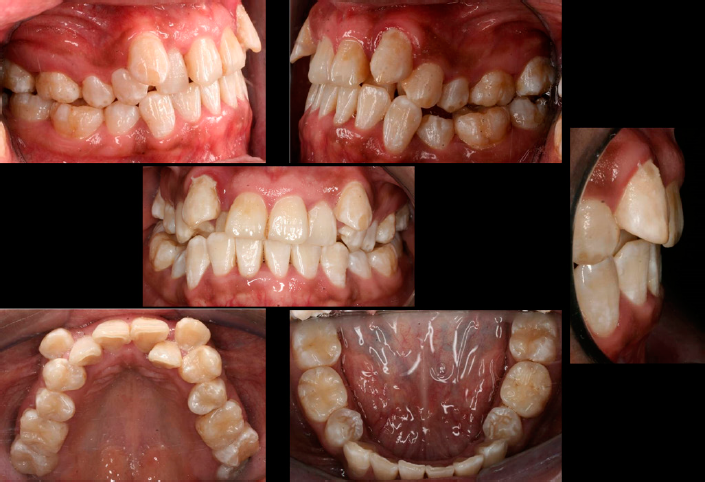

En el análisis facial se determinó una paciente dolicofacial con el tercio inferior aumentado, exposición disminuida de los dientes anteriores superiores al sonreír y perfil recto (Figura 1). A la exploración clínica se identificó dentición permanente con ausencia de los dientes 34 y 44, periodonto reducido estable, mucosa bien irrigada, frenillos bien implantados, líneas medias no concordantes, apiñamiento superior severo e inferior moderado; dientes 13 y 23 en supraoclusión Clase III molar, y mordida cruzada unilateral (Figura 2). Se solicitaron auxiliares diagnósticos incluyendo ortopantomografía y radiografía lateral de cráneo (Figura 3).